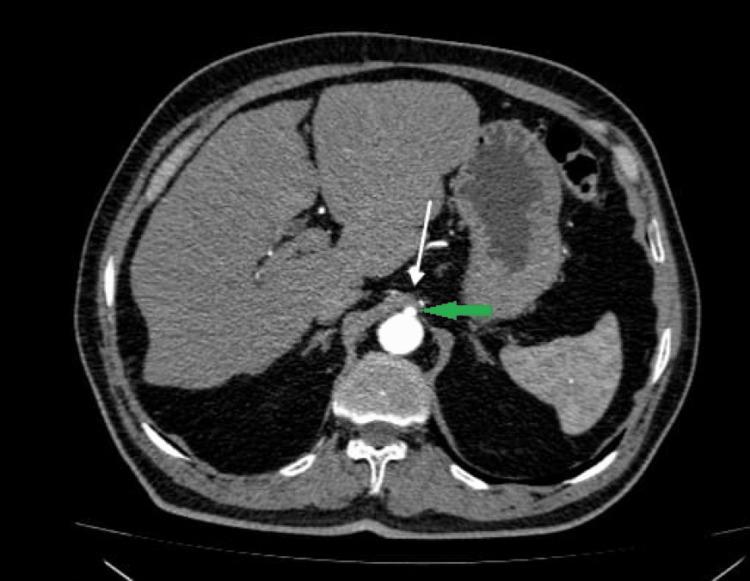

Celiac artery compression syndrome (CACS) is an uncommon and poorly understood condition. Compression of the celiac artery by the median arcuate ligament causes intractable postprandial abdominal pain, weight loss, vomiting, and nausea. We present a case of a 68-year-old male who suffered recurrent severe episodes of postprandial abdominal pain associated with occasional nausea, vomiting, and elevated blood pressure. The diagnostic workup was significant for celiac artery compression on computed tomography angiography. Diagnosis of CACS was made after the exclusion of the other possible pathologies, and the patient was referred to the surgical team for further management for median arcuate ligament release on an elective basis.

腹腔干压迫综合征(CACS)是一种罕见且了解甚少的病症。正中弓状韧带对腹腔干的压迫会导致顽固性餐后腹痛、体重减轻、呕吐和恶心。我们报告一例68岁男性患者,他反复出现严重的餐后腹痛发作,伴有偶尔的恶心、呕吐和血压升高。计算机断层血管造影显示腹腔干受压,这在诊断检查中具有重要意义。排除其他可能的病理情况后,确诊为CACS,该患者被转介至外科团队,择期进行正中弓状韧带松解的进一步治疗。